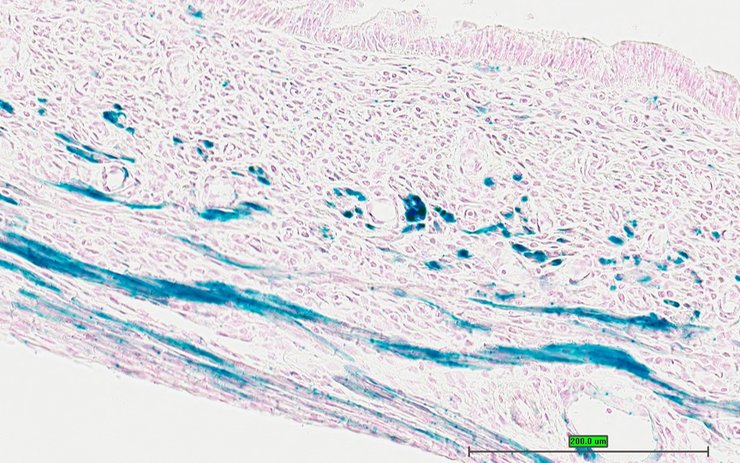

TS28: skin Present UC Davis_1886162

Specimen UC Davis_1886163: postnatal adult; Gas6tm1.1(KOMP)Vlcg/Gas6+ (more )

Structure Level Pattern Image Note

TS28: skin Present UC Davis_1886163